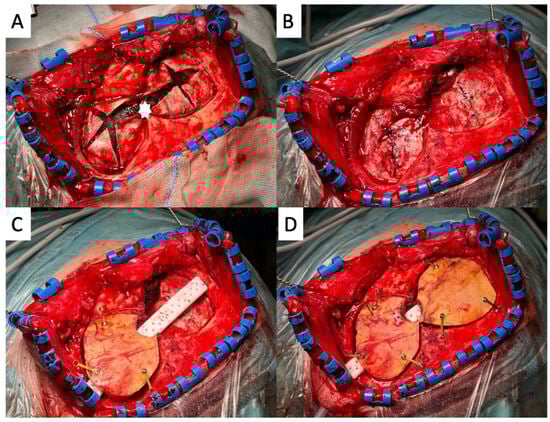

Figure 3. An intraoperative view of the endless-loop craniotomy procedure for revision surgery. White asterisks mark the former burr hole. (A): Endless-loop craniotomy was performed, involving the wide, curved exposure of the dura mater with the T-incision flap retracted anteriorly. (B): The dura mater was incised in a visualized manner, allowing for the wider exposure of the subdural space. White asterisks mark the pre-existing position of the dura opening. (C): The subdural hematoma was visualized, with its “cranificated” appearance and its inhomogeneous, firm consistency.